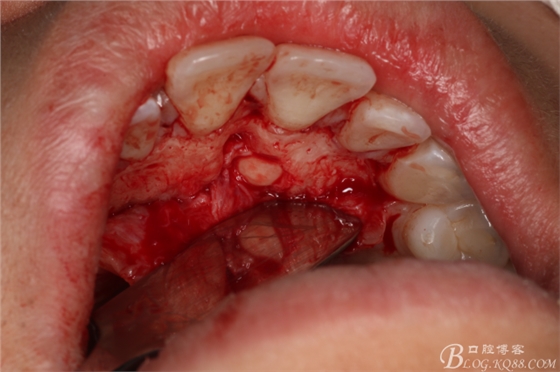

圖7.翻瓣

圖8.翻瓣暴露出鼻腭神經(jīng)管及腭側(cè)骨面